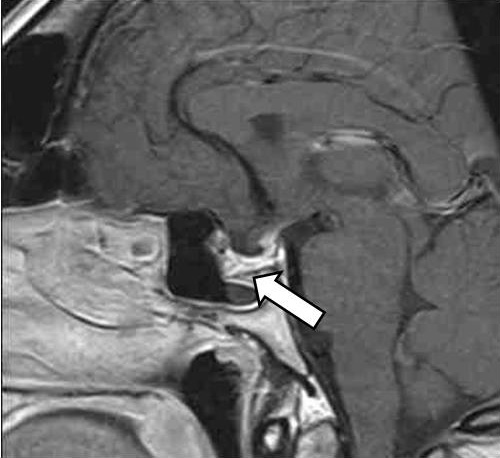

Женщина 42 лет 09.12.2020 была доставлена бригадой скорой медицинской помощи с подозрением на острое нарушение мозгового кровообращения в приемное отделение БУЗ УР «1 РКБ МЗ УР» с жалобами на сильную головную боль в лобной области, повышение артериального давления (АД) до 160/100 мм рт. ст., общую слабость, повышение температуры тела до 37,5 °C, по поводу чего принимала метамизол натрия без эффекта. По результатам компьютерной томографии головного мозга данных за острое нарушение мозгового кровообращения выявлено не было; обнаружена макроаденома гипофиза размерами 28 × 21 × 22 мм с интра-, инфраселлярным ростом, распространявшаяся из гипофизарной ямки через разрушенное дно турецкого седла в полость основной пазухи. По данным далее проведенной магнитно-резонансной томографии (МРТ) гипофиза с контрастированием подтверждена макроаденома гипофиза размерами 22 × 32 × 23 мм с супра-, инфра-, латероселлярным ростом с компрессией воронки гипофиза, хиазмы зрительных нервов слева, охватом внутренней сонной артерии с двух сторон (рис. 1). Гормональное исследование от 12.01.2021: ИФР-1 – 49,8 нг/мл (43–209)1 [1]. При компьютерной сферопериметрии выявлены единичные периферические относительные скотомы, абсолютные скотомы правого глаза и рассеянные относительные скотомы левого глаза.

Рис. 1. Магнитно-резонансная томография гипофиза с контрастным усилением, Т1-взвешенные изображения. Визуализируется макроаденома гипофиза с супра-, инфра-, латероселлярным ростом с кровоизлиянием (указана стрелкой)